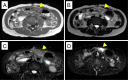

A 44-year-old woman presented to our hospital with abdominal pain. Abdominal ultrasonography and computed tomography showed a mass-like change in the lesser omentum between the liver and stomach. Esophagogastroduodenoscopy revealed a submucosal tumor-like change, and endoscopic ultrasonography (EUS) revealed that the mass was located outside of the stomach wall. We performed EUS fine-needle aspiration and diagnosed panniculitis of the lesser omentum. Based on these findings, we suggest that mass-like lesions in the lesser omentum and submucosal tumor-like changes in the anterior wall on the lesser curvature side of the stomach be evaluated for the possibility of panniculitis of the lesser omentum.